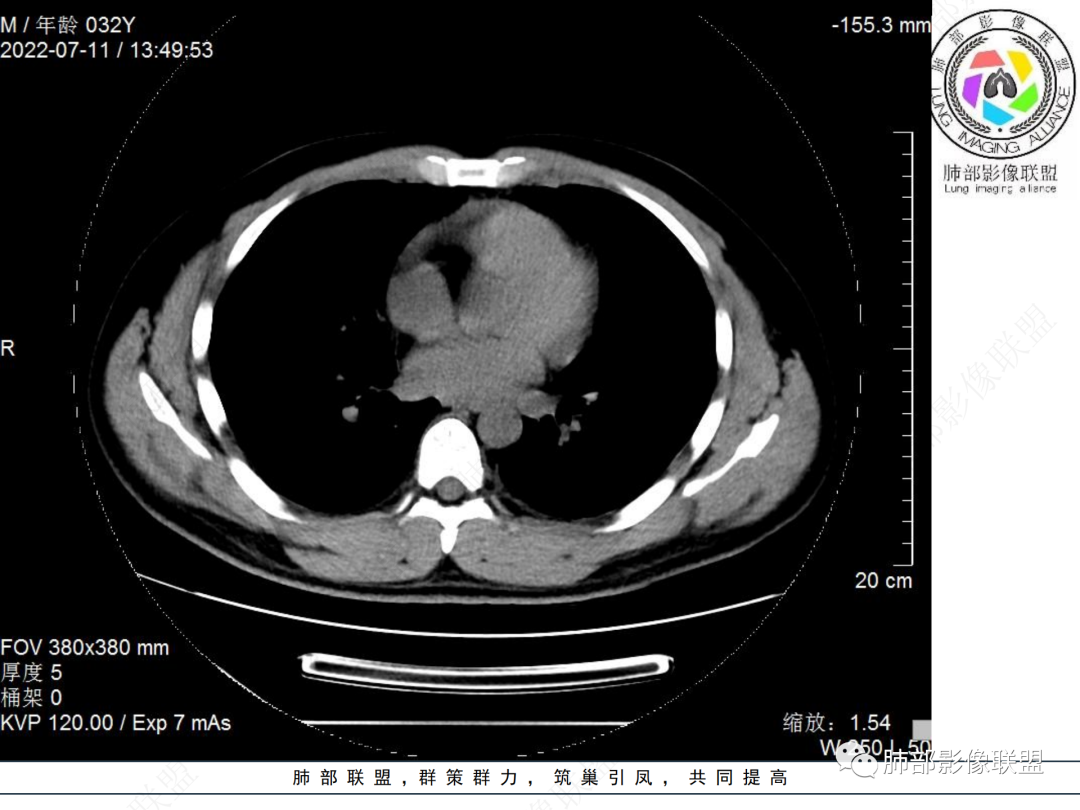

左肺下叶后基底段开口处结节,边缘光滑清楚,没有增强扫描,年轻男性患者痰血三天,考虑1.良性病变:腺瘤、错构瘤、平滑肌瘤

2.恶性:类癌、粘液表皮样癌。

左肺下叶外后基底段气管内见结节状影,边缘部分清晰。考虑错构瘤,待排恶性病变。

左肺下叶气管内外占位病变,咯血病史,考虑类癌,粘表待排。

青年男性,左肺下叶后基底段支气管开口软组织结节,边缘光整,气管镜提示质软,易出血,考虑类癌

左肺下叶后基底段开口处结节,边缘光滑清楚,年轻患者考虑鳞癌或腺样囊腺癌

左肺下叶气道腔内占位,远端无花花草草,疾病谱:鳞,类癌,粘表,腺样囊腺癌,小,无增强,不好判断,临床咯血,选类癌。

大支气管腔内结节,考虑类癌

左肺下叶后基底段开口处结节影,边缘光滑,患者年龄较小,首选类癌

男性,咳血左肺下叶支气管腔内结节影,没有阻塞性炎症,考虑类癌,鳞癌

年轻男性,支气管内结节,首先类癌

左肺下叶后基底段开口处腔内见壁结节,花生米样,宽基底,补充增强及矢状位重建,确定我无向壁外突破浸润生长,另见强化的特点,临床触之易出血,类Ca可能性大。

年轻男性,支气管腔内占位,边缘尚平整,年轻人,首先类癌,鉴别错构

年轻男性,咳血,左肺下叶后基底段支气管腔内结节,边缘光滑,首先考虑青年三件套,类癌大于粘液表皮样癌,支气管镜质软,触之易出血,鉴别血管瘤,平滑肌瘤

左肺下叶后基底段开口部结节,密度较均匀一致,边缘较光整,目测密度偏低,支气管镜示:质软、触之易出血,考虑恶性,类癌。

支气管腔内结节,有蒂与支气管壁连接,考虑良性病变可能性大,支气管错构瘤 血管瘤一类的

左肺下叶后基底段支气管腔内结节,有蒂,容易出血,先考虑良性病变,肉芽组织型血管瘤,与类癌鉴别。

青年男性,左肺下叶后基底段支气管开口软组织结节,边缘光整,气管镜提示质软,易出血,考虑恶性类癌

左肺下叶后基底段开口处结节影,边缘光整,年轻患者,伴咯血,考虑鳞癌,类癌不能排除